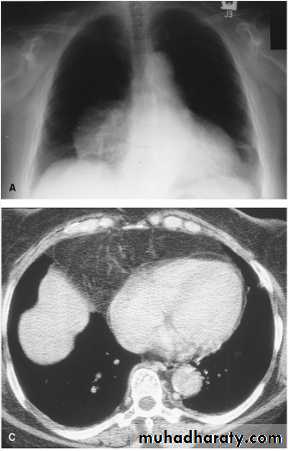

Massive pleural effusion with mediastinal shift to the left.

(A) Chest radiograph(B) CT coronal reconstruction. A massive effusion displaces the mediastinum to the left. CT shows the important pleural effusion together with the enhanced atelectatic left lung.

Note also the depression of the right hemidiaphragm (arrows).